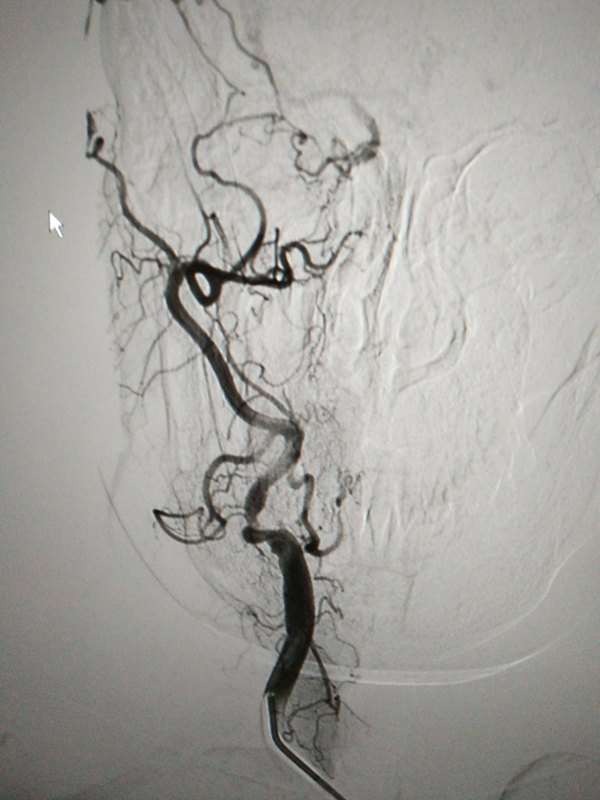

腦梗塞既人們常說的“中風(fēng)”的主要原因是腦供血?jiǎng)用}的狹窄和閉塞。據(jù)統(tǒng)計(jì),60%以上的腦缺血病人是由頸動(dòng)脈狹窄引起。 頸動(dòng)脈是人腦的主要供血?jiǎng)用}之一,當(dāng)出現(xiàn)不同程度的狹窄時(shí),大腦也就出現(xiàn)不同程度的缺血。主要的表現(xiàn)為:耳鳴、視物模糊、頭痛、頭暈、記憶力減退、乏力、嗜睡、失眠以及多夢(mèng)等。也可以出現(xiàn)眩暈、眼前發(fā)黑(黑矒),重者可以出現(xiàn)反復(fù)的暈厥,甚至偏癱、失語、昏迷,少數(shù)人可以有視力下降,偏盲、復(fù)視,甚至突發(fā)性失明。 頸動(dòng)脈狹窄的治療方式有三種:藥物治療、頸動(dòng)脈內(nèi)膜剝脫術(shù)和頸動(dòng)脈支架植入術(shù)。 藥物治療是長(zhǎng)期服用抗血小板藥(如常規(guī)服用阿司匹林、或新的強(qiáng)效抗血小板藥物氯吡格雷),但僅適用于狹窄程度不超過50%的患者,對(duì)于超過70%狹窄的患者一般建議手術(shù)治療。 頸動(dòng)脈開刀手術(shù)的基本方法是內(nèi)膜切除,解除動(dòng)脈狹窄和粥樣硬化斑塊,恢復(fù)大腦血供,消除腦梗塞栓子,該手術(shù)的缺點(diǎn)是需要全身麻醉,頸部切口及創(chuàng)傷大,恢復(fù)慢,優(yōu)點(diǎn)是完全切除增生內(nèi)膜和硬化斑塊,再發(fā)生狹窄的機(jī)會(huì)較小,不需要終身服用抗血小板及抗凝藥物。 頸動(dòng)脈支架植入術(shù)具有創(chuàng)傷小、操作簡(jiǎn)單、起效快、恢復(fù)快、療效確切、可重復(fù)操作的優(yōu)點(diǎn)。只需要局部麻醉,在大腿根部穿刺,將一根直徑在2毫米左右的導(dǎo)管放置入股動(dòng)脈,將導(dǎo)管輸送到頸動(dòng)脈狹窄部位,選準(zhǔn)位置后將支架釋放出來就完成了對(duì)頸動(dòng)脈硬化狹窄部位的擴(kuò)張成型,改善大腦血流供應(yīng)。 當(dāng)出現(xiàn)以下情況時(shí)需進(jìn)行手術(shù)或腔內(nèi)治療:1、頸動(dòng)脈狹窄程度超過70%;2、頸動(dòng)脈狹窄程度小于70%,但頭暈、黑矒等腦缺血癥狀典型,或者硬化斑塊不穩(wěn)定,容易脫落;3、藥物治療效果不佳,有中風(fēng)發(fā)作史,或腦梗塞后仍有小中風(fēng)發(fā)作。 病例介紹如下: 女性,69歲,主主因間斷性黑懵,頭暈入院,無四肢肌力、肌張力障礙,既往無糖尿病病史,高血壓病史多年口服降壓藥物控制平穩(wěn),當(dāng)?shù)蒯t(yī)院彩超提示雙側(cè)頸內(nèi)動(dòng)脈重度狹窄就診我院,頭頸部CTA顯示右側(cè)頸內(nèi)動(dòng)脈長(zhǎng)段閉塞,左側(cè)頸內(nèi)動(dòng)脈起始端極重度狹窄,右側(cè)椎動(dòng)脈起始端重度狹窄。治療策略先行右側(cè)椎動(dòng)脈支架植入,目的防止因頸動(dòng)脈支架植入過程中血壓波動(dòng)造成后循環(huán)梗塞可能,而后再行左側(cè)頸動(dòng)脈支架植入,過程如下圖所示: 頸動(dòng)脈狹窄行支架植入術(shù)的效果鼓舞人心,患者的接受程度也很高,國(guó)際上很多對(duì)比內(nèi)膜切除術(shù)和支架成型術(shù)試驗(yàn)的結(jié)果表明,頸動(dòng)脈支架成型術(shù)較內(nèi)膜切除術(shù)安全、創(chuàng)傷小、恢復(fù)快。 對(duì)于接受頸動(dòng)脈支架植入的患者而言,金屬支架是異物,在體內(nèi)與血液接觸時(shí)有血小板聚集和形成血栓的可能,因此術(shù)后需正規(guī)口服抗凝、抗血小板藥物。通常用藥為阿司匹林100mg,1次/日,口服終身,波立維(氯吡格雷)75mg,1次/日,口服3-6個(gè)月。術(shù)后1,3,6,9,12個(gè)月時(shí)復(fù)查頸動(dòng)脈超聲或CT,以后每年復(fù)查一次。術(shù)后維持良好的生活習(xí)慣:嚴(yán)格戒煙、清淡低鹽低脂飲食;積極活動(dòng)鍛煉身體;積極控制好血壓、血糖及血脂水平。